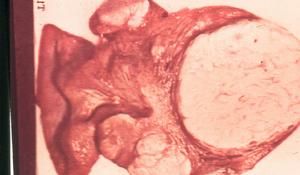

圖11.大體標本檢查

(1)子宮常增大一般呈均勻性增大,也可不規則增大質軟。

(2)腫瘤多數為單個,體積較大,以肌壁間多見,漿膜下和黏膜下少見。

(3)腫瘤可有清楚的假包膜,也可瀰漫性生長,與肌層界限不清。

(4)切面:由於腫瘤生長迅速,可出現出血、壞死,切面呈魚肉狀典型的鏇渦結構消失,有灶性或片狀出血或壞死時,很難與子宮肌瘤紅色變性區分。

(4)壞死:腫瘤細胞有3種壞死即凝固性壞死(coagulatiate tumor cell necrosis)、透明性壞死(hyalinenecrosis)和潰瘍性壞死(ulcerative necrosis)。平滑肌肉瘤以凝固性壞死為主,其特徵為壞死灶與周圍組織的轉變突然其間無肉芽組織或透明變性的結締組織為中間帶。有學者認為組織壞死是診斷子宮平滑肌肉瘤的不可或缺的指標(圖1)。